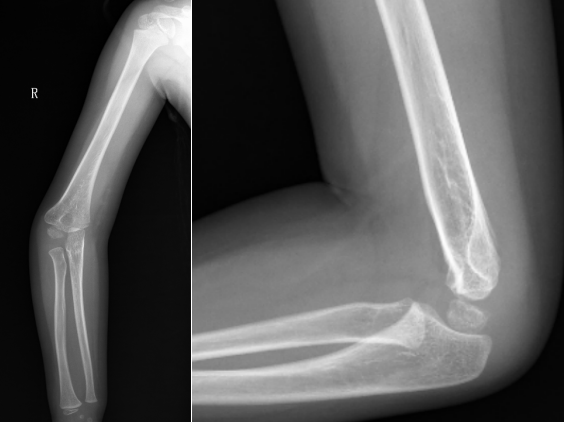

病例1:小明(化名)、男、12岁,8年前因摔伤致“左肱骨髁上骨折”,于外院行手术治疗,手术后逐渐发生左肘内翻畸形。

受伤当时的X线片

手术后X线片

该例患者虽行手术治疗,但从术后X线片上分析其骨折端旋转畸形矫正不充分,残余肱骨远端的内旋畸形,所以术后逐渐发生肘内翻畸形。针对该患者我们实施了手术矫形治疗。